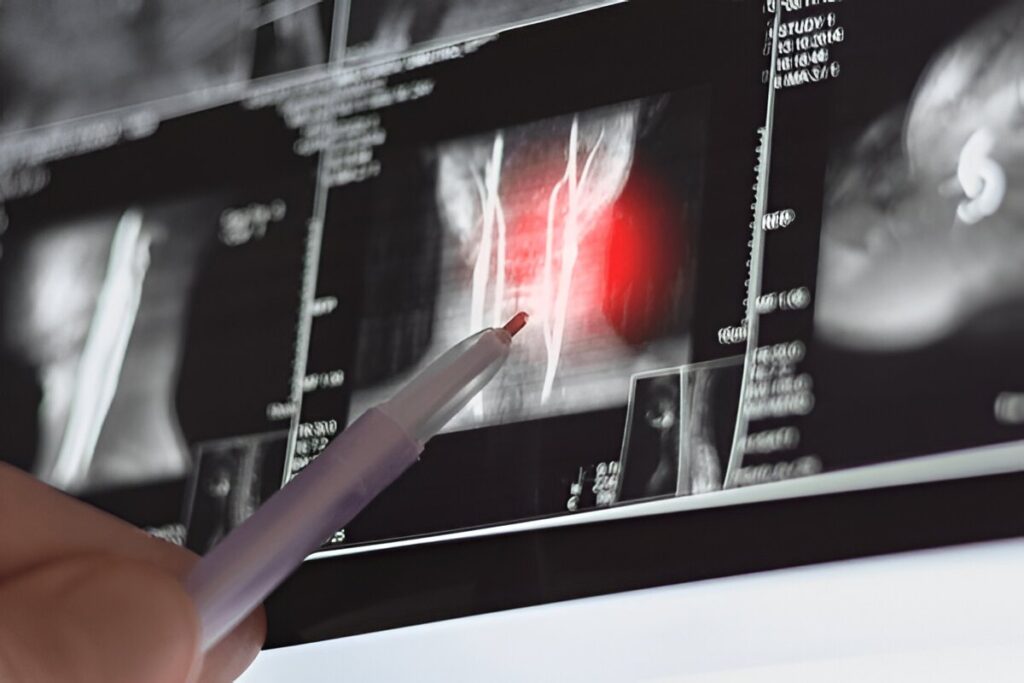

4. Nerve-Related Neck Pain (Cervical Radiculopathy)

Nerve-related neck pain, also known as cervical radiculopathy, occurs when cervical nerve roots become irritated or compressed.

Symptoms

- Neck pain radiating into the arm

- Tingling or numbness

- Muscle weakness

Physiotherapy Treatment:

Physiotherapy focuses on spinal unloading, posture correction, and nerve mobility exercises to reduce nerve-related neck pain.